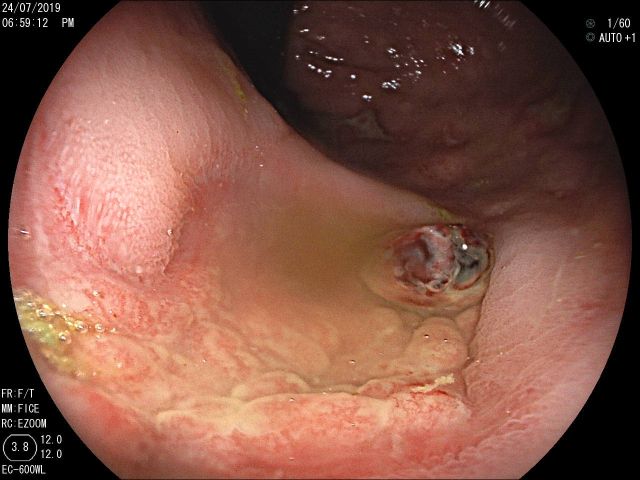

A messy web

1º Prémio - Fotografia